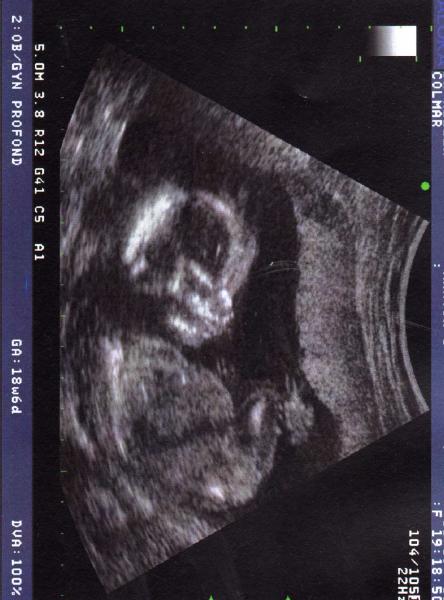

Apres le stress....

Voila je vous presente ma fille... (oula va falloir que je m'y fasse!) Mademoiselle, est un peu plus petite que son grand frere au meme moment ... 11cm de la tete au coxcys et 15cm de la tete aux pieds. Elle va bien, son petit coeur bat bien aussi...

Pour les malaises, c'est bon, d'apres le gynéco c'est rien de grave, juste que la miss me puise tout l'oxygene alors desfois ben... j'ai du mal... a respirer oui oui...

Brian a pu assister a L'echo tout content d'ailleur!